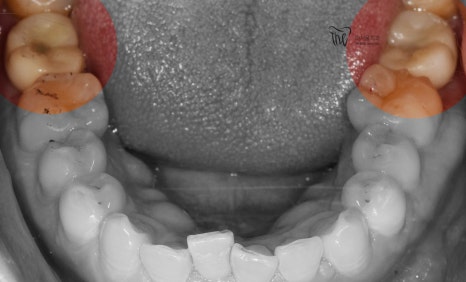

시간이 흘러, 중간중간 f.u 을 거침에 따라서

지르코니아 크라운까지 연결을 해드리면서

시술 과정은 모두 종료가 됩니다.